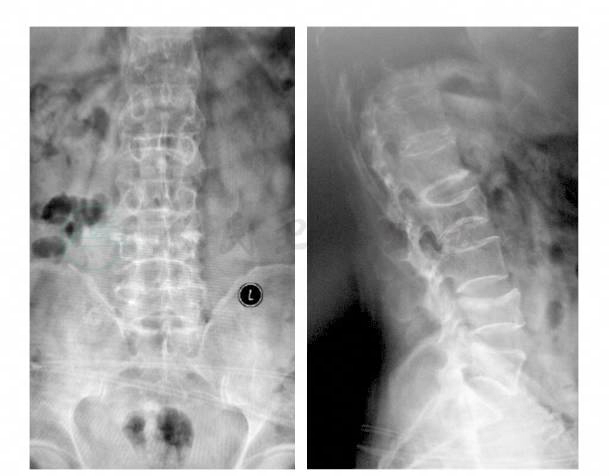

患者,男性,61岁。患者入院前5个月摔伤腰部,当即感到腰部疼痛并活动受限。当时于外院行X线片检查提示L2椎体压缩骨折,卧床休息保守治疗,1个月前站立活动时仍觉腰部疼痛较重,保守治疗效果不佳,为求进一步治疗以“T11、L2、L4椎体骨折”收入院。既往患有先天性二尖瓣关闭不全,平素活动无明显不适。查体:腰部屈伸活动明显受限。腰背部叩痛明显,L4棘突压痛,双下肢活动感觉正常。辅助检查:X线片提示T11、L2椎体压缩骨折,骨质疏松,退行性骨关节病。MRI:T11、L2、L4压缩性骨折,T11、L4骨髓水肿,L2陈旧骨折,腰椎退行性骨关节病(图1)。

图1 T11、L2椎体压缩骨折X线片